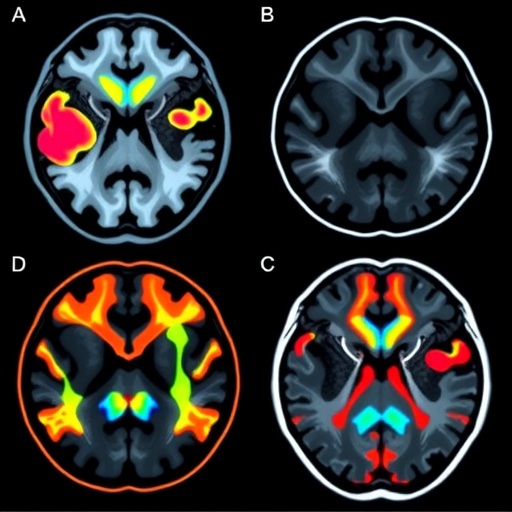

Central to this study is neuromelanin-sensitive MRI, a relatively recent innovation that exploits the paramagnetic properties of neuromelanin—a dark pigment concentrated primarily in the substantia nigra pars compacta (SNc), a brain region severely implicated in Parkinson’s pathology. Neuromelanin accumulates in dopaminergic neurons, and its depletion is a hallmark of PD-related neurodegeneration. By highlighting neuromelanin-rich areas, this imaging modality serves as a window into neuronal integrity and loss, enabling researchers to visualize pathological changes that were previously inaccessible using conventional MRI sequences.

Complementing neuromelanin mapping is the T1w/T2w ratio imaging technique, which accentuates tissue contrast by dividing the signal intensities from T1-weighted and T2-weighted MRI sequences. This ratio has proven effective in delineating microstructural brain changes, including myelin density and iron deposition, which are altered in neurodegenerative diseases. When applied alongside neuromelanin-sensitive imaging, the combined approach enables a multidimensional characterization of brain pathology, capturing both neuronal loss and associated tissue integrity changes.

The researchers conducted a comprehensive analysis involving patients diagnosed with tremor-dominant PD and those with essential tremor, rigorously matched for clinical variables. Their neuroimaging protocol included high-resolution neuromelanin-sensitive sequences targeting the substantia nigra and locus coeruleus—another critical neuromelanin-containing area—combined with T1w/T2w ratio maps covering basal ganglia and cortical regions pertinent to motor control. Quantitative metrics were extracted, providing objective biomarkers reflective of the underlying neuropathology.

Findings revealed distinct neuromelanin signal attenuation in the substantia nigra of Parkinson’s patients compared to essential tremor subjects, consistent with selective dopaminergic neuron degeneration. Notably, the extent of neuromelanin loss showed a strong correlation with clinical measures of bradykinesia and rigidity, reinforcing its relevance as a PD-specific marker. On the other hand, essential tremor patients exhibited preserved neuromelanin signals but demonstrated subtle alterations in the T1w/T2w ratio within cerebellar regions, implicating cerebellar microstructural changes unique to ET pathophysiology.

Technically, the neuromelanin-sensitive sequences harness magnetization transfer contrast and optimized inversion recovery parameters to maximize contrast-to-noise ratio of neuromelanin-rich clusters. When fused with T1w/T2w ratio maps derived from standardized brain segmentation frameworks, the protocol offers reproducible, high-resolution brain images suitable for both clinical implementation and research investigations. Future refinements may integrate machine learning algorithms to automate region-of-interest delineation and enhance diagnostic accuracy.